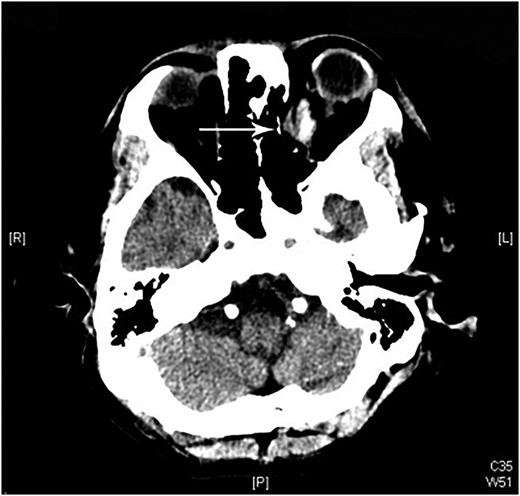

A 60-year-old man was admitted to our medical ward due to aspiration pneumonia. He had a medical history of diabetes mellitus, end-stage renal disease; a tuberculosis bacilli-related thoracic spine infection with paraplegia, and a previous coronary artery bypass graft. During his third day at the hospital, he obtained a ballpoint pen and inserted it into his left eye. On physical examination, the patient appeared to be alert with normal vital signs. The ballpoint pen protruded from his left upper eyelid; it was firmly lodged in his left medial orbit between the globe and nose, causing left eye proptosis (Fig. 1). Neurologic examinations revealed that the patient was neurologically intact except for complete left ophthalmoplegia. Brain CT scanning revealed a tubular foreign body that was located in the anteroposterior plane extending from the orbital apex and directly into the parasellar region (Fig. 2). The metallic portion of the foreign body was entrapped in left optic canal (Fig. 3). There was no evidence of intracranial hemorrhaging or a rupture in the globe (Fig. 4). The patient was treated with high-dose steroids to protect the optic nerve. The plastic ballpoint pen and metallic tip was withdrawn from the orbit smoothly at bedside, and no craniotomy was required. The ballpoint pen had been inserted to an estimated depth of 7 cm through the eyelid and into the orbit. The patient was then transferred to the ICU for close neuro-observation. We initiated intravenous broad-spectrum antimicrobials and vancomycin therapy and continued these medications for three weeks. A psychiatrist was consulted for a complete psychiatric evaluation and suicide prevention. The follow-up CT scan showed no retained foreign bodies or intracranial hemorrhaging (Fig. 5). At the last follow-up examination 2 months after the injury, the patient presented with complete left ophthalmoplegia and blepharoptosis but intact visual function.

The ballpoint pen tip reaches into the parasellar region via the optic canal.